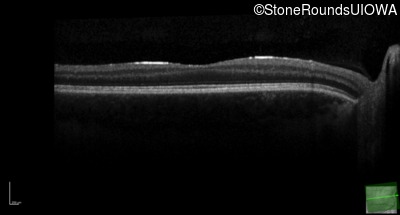

Age at visit: 17 years

This 17 year old male had normal vision until about 6 months earlier when he began to lose central vision. The left eye may have been affected prior to the right eye.

Diagnosis & molecular findings

Leber Hereditary Optic Neuropathy MT-ND4 11778 A>G   MT